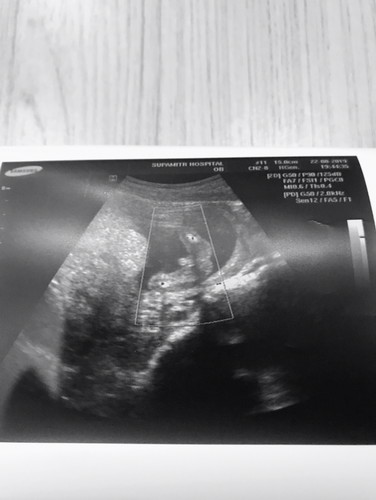

ผญ หรือ ผช ค้ะ หรือเป้นสายสะดื้อ

อยากทราบว่าเป้นผฐหรือผช หรือที่เห้นเป้นสายสะดื้อค้ะ ขอคำแนะนำหรือดูใบอัลตราซาวที่แม่ๆใด้ผช กันหน่อยจ้า

ของแม่น่าจะชายนะคะ มีจู๋ รูปซาวด์ของแม่บ้านนี้หมอก็บอกว่าชาย แม่ก็ไม่แน่ใจเหมือนกันค่ะว่าสายสะดือไหม ไม่รู้ว่าน้องอยู่ในท่าอะไรด้วย😅